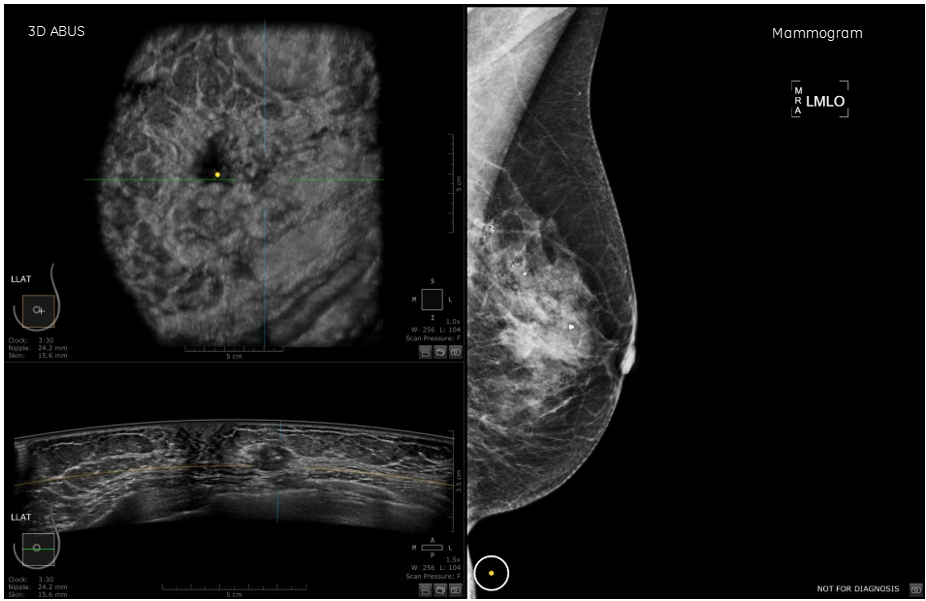

Saving Lives with 3D Breast Ultrasound & Mammography Empowered Women

From www.volusonclub.net

Saving Lives with 3D Breast Ultrasound & Mammography Empowered Women What Is 3D Breast Imaging A 3d mammogram is an advanced breast cancer screening tool. It also helps us catch more cancers. Your doctor might call it digital. Studies show that this technology increases the detection of invasive breast cancers. What is a 3d mammogram? It does so by detecting characteristic masses (tumors) or calcium deposits called microcalcifications that may be an early sign of. What Is 3D Breast Imaging.